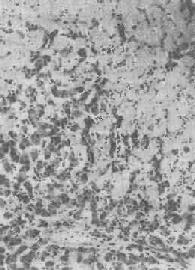

肾近曲小管上皮细胞玻璃样小滴变

图1-21 肾近曲小管上皮细胞玻璃样小滴变

上皮细胞胞浆内出现大小不等的均质圆形小滴